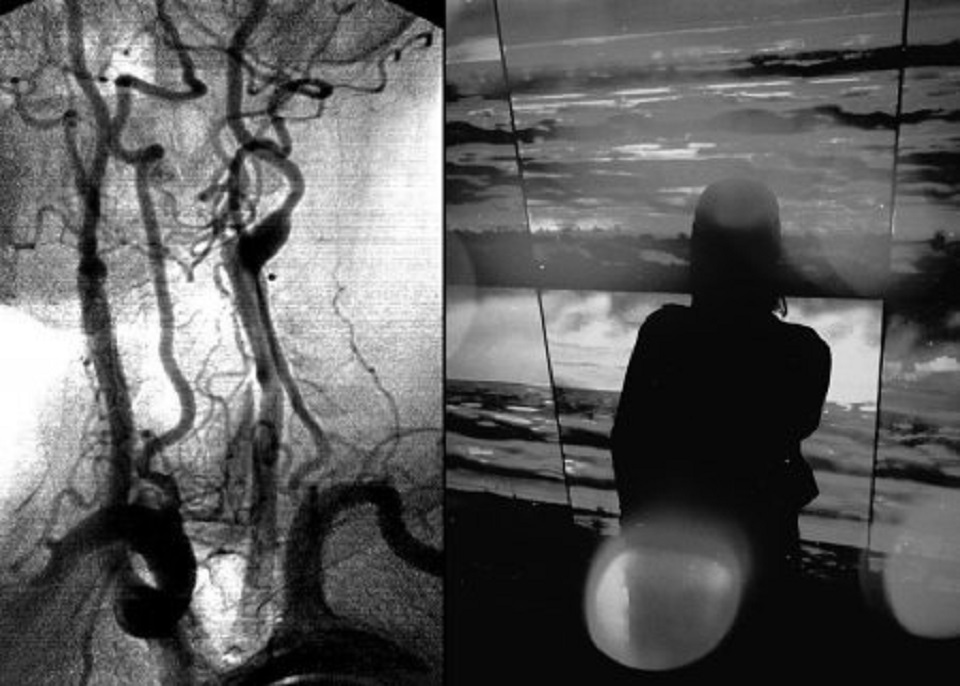

Галерея «Улица Малевича» приглашает выставку «B&W reflections». Коллажи с абстрактной черно-белой фотографией и рентген-ангиограммами авторства Алины Сафроновой будут экспонироваться с 7 июня по 4 сентября 2022 года на третьем этаже Музея современного искусства «Артмуза». Музей работает ежедневно с 11:00 до 22:00.

Серия Tree of Life посвящена теме гармонии слияния внутреннего и внешнего. Изображения кровеносной системы сопоставляются с абстрактными черно-белыми кадрами, намекая на единство всего живого и предлагая воспринимать произведение как живой механизм. Вторая серия Abstractions фокусируется на дыхании города в моменте. Через детали, отрезки, осколки, линии автор предлагает исследовать общество, как единый живой организм.